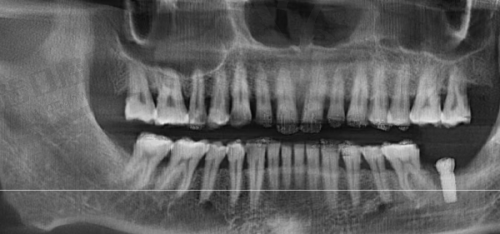

儀器新過香港:深圳啲大診所好多都有「AI智能種牙機械臂」(拜博口腔)、3D導航種植系統,香港好多中小型診所仲用緊傳統X光,「深圳醫生話我牙骨密度唔夠,用3D掃描即刻計出種植角度,香港舊儀器根本做唔到」(住荃灣嘅OL阿詩分享)。